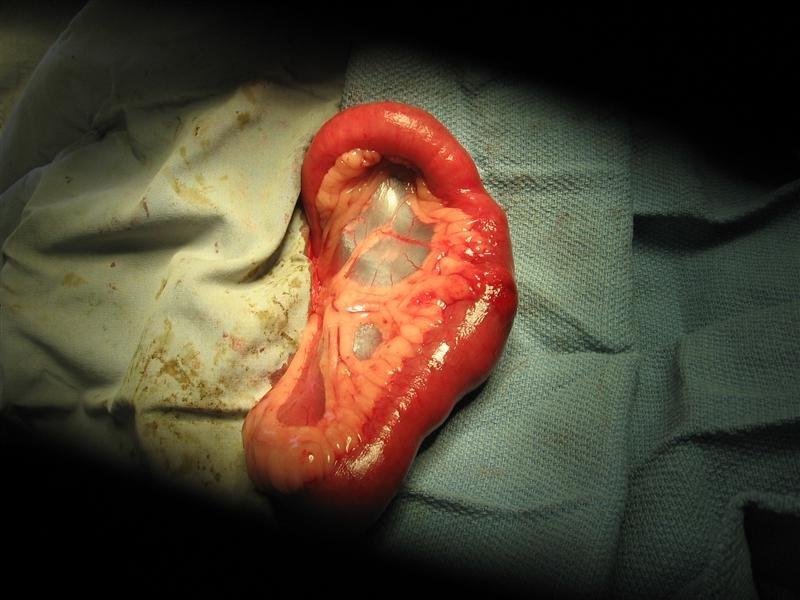

BHRR’s Barkley is healing really well and I took a new picture tonight of his incision area and will add ASAP. He has had a small ‘bump’ just on the side of his incision as it has been healing and it has not pained him yet tonight I noticed it was larger and took a closer look at it. It causes him no discomfort to examine or touch, is not red, swollen etc. yet I will feel better to have a recheck done on him and shall see about getting him in on April 30th if I can when I work that day. Probably just scar tissue inside. I also want to get an updated weight on him to see how he is doing! Tonight, Sean also held him while I did his nails. This was the first time we have done his nails for we had them done last time when he was under having his obstruction surgery. His back nails no problem at all but his front nails…not so good. He was scared and slightly peed the poor dog and he was full of ‘bluff’ growling and I had not even started doing those nails yet. A lesser experienced person would have been intimidated. It made us sad to see him that way yet Barkley had a strong constitution to try to ‘bully’ and ‘bluff’ to get us not to do his nails, yet that was not going to happen for it is clear that in the past in his own home(something his previous owners had also mentioned to me plus is in his file at KAH), this behavour had been used and he ‘won’ and got his way. He was reassured, patted and I went along calmly to get his nails done. When I was done, he wanted in his crate and we let him in as that is his ‘safe’ spot and I gave him a special treat which he took with that really cute wagging nub of a tail. This was confirmation that he had to have had some bad experience in the past, he was nervous and that by trying to be intimidating, he had been given his way. The wagging tail and willingness to take the treat proved that he is just a big sweet baby in the right hands and that the ‘bluffing’ and attempting to ‘bully’ is not going to be tolerated YET how we handled this inappropriate behavour was most important. We did not get upset, angry, panic or scared. He was given a calming word, touch and onward bound we went. NO big deal is how we handled it and to Barkley after he was in his crate, it truly was not a big deal. We shall see what next week brings when it is time to do his nails again, for I want his front feet handled often with those clippers. So, for those wanting to understand this behavour, Barkley exhibited both fear and ‘intimidation’ in regards to his nails. This boy still has some mental rehab to do before he shall be ready for adoption and he shall not go to a home that is inexperienced with Dobermans. I woud like to see him in a home with at least one other dog, male or female is of no matter as long as they are compatible with BHRR’s Barkley in respect to sociability and his playfulness level. Barkley has loved all the dogs and kids and people he has met to date. Barkley is just completely enamored with BHRR’s Porridge and he and BHRR’s Storm could walk in circles all day long as they keep trying to sniff each other’s rumps! LOL For those that have been to our home, you will most understand what I mean in regards to his comfort zone with our hardwood floors from just at Sean’s desk on the main floor to the TV on the other side and from the water bowl at the fireplace to the door to the sunroom. That is his ‘comfort’ area and he will not venture further at this time. At one point, he found himself close to the kitchen area and when he realised, he froze, did that ‘Dobie’ whine and scurried back into his comfort zone. Barkley now has a Kuranda Bed in his Crate, compliments of BHRR’s Potter lending him his as in his ‘feedback’ to me at one point when I put him into his crate for a ‘time out’, he decided to try and shred up his blankets for the first time and so, bye-bye blankets! The look on his face! LOL Dobies can be notorious for chewing and ingesting things they should not and his new home is going to have to be really careful about what Barkley has access to. When we go out, even if it is for me to put the kids on the bus; he is in his 45″ collosal crate. There shall be no opportunities for Barkley to be put into a situation of failure here to obtain another possible obstruction. He is not allowed stuffies and all toys that he is allowed to play with and he loves to playbow and play when he feels like it; are closely supervised. Barkley could eat all day if you let him and I now feeding him three times a day and he is getting his hill work every morning with me to build up muscle. He has gotten much better about sharing the water bowl and if a dog is strong enough to call his ‘bluff’, he backs down gracefully and waits his turn or shares the water bowl. GOOD boy Barkley! It is clear that he will test you and does test us, more myself than Sean and that the more guidance and consistency of training he is getting, he is becoming that much better with his own behavour stability. I cannot wait to see how things are going to be once we take the e-collar off him and he is also out of his honeymoon period! It is also going to be very revealing to see how he is when it comes to bath time for as the spring mud is drying up, the dogs are a bit dusty and with the warmer weather comes baths! YAY! We are still trying to raise another $822.78 for his BEGGING FOR BARKLEY Fundraiser and deepest thanks being sent to everyone that has believed in him to reach out to support Barkley! If all goes well, my hope is to have BHRR’s Barkley placed up for adoption within the month. 🙂 This will depend on how far he has come more with his mental rehab and his obedience for Barkley also likes to get into that ‘selective’ hearing mode. OMG! It is so funny to see yet as I have often been told ‘Gwennie invented the word stubborn’and he has more than met his match in that department! 😉 😀 I am having so much fun with Barkley in the house! He has been a real treat to have here with us! Something that I have not yet mentioned is that from the very first night he arrived, I found his ‘spot’ and it is just under his chin and he loves loves loves to have it rubbed. He will lean into you and just sigh with pleasure. 🙂

BHRR’s Barkley is healing just wonderfully from his obstruction surgery on April 1st and we continue to thank everyone who has assisted him to date with his BEGGING FOR BARKLEY Fundraiser! I am adding 2 pictures below from April 10th, 2010 and I have so many yet to put together for his slideshow. His sutures were subcutaneous yet you can see how well his incision is looking! Tonight, BHRR’s Barkley is going to help make a TON of homemade cinnamon buns; so that I can bring them into the Hospital with me tomorrow to THANK all the great staff that I work with that pulled together to save his life. It cannot be said enough, what a miracle story Barkley is! He could really use some more financial support to finish paying off his extensive Vet/Rehab Bills and on behalf of BHRR’s Barkley, I humbly thank everyone in advance for your consideration.

BHRR’s Barkley (2.5+) – April 10th, 2010